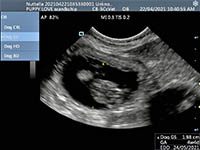

Mobile Ultrasound Pregnancy Scanning and Microchipping Services

Puppy Love scan and chip

Gallery